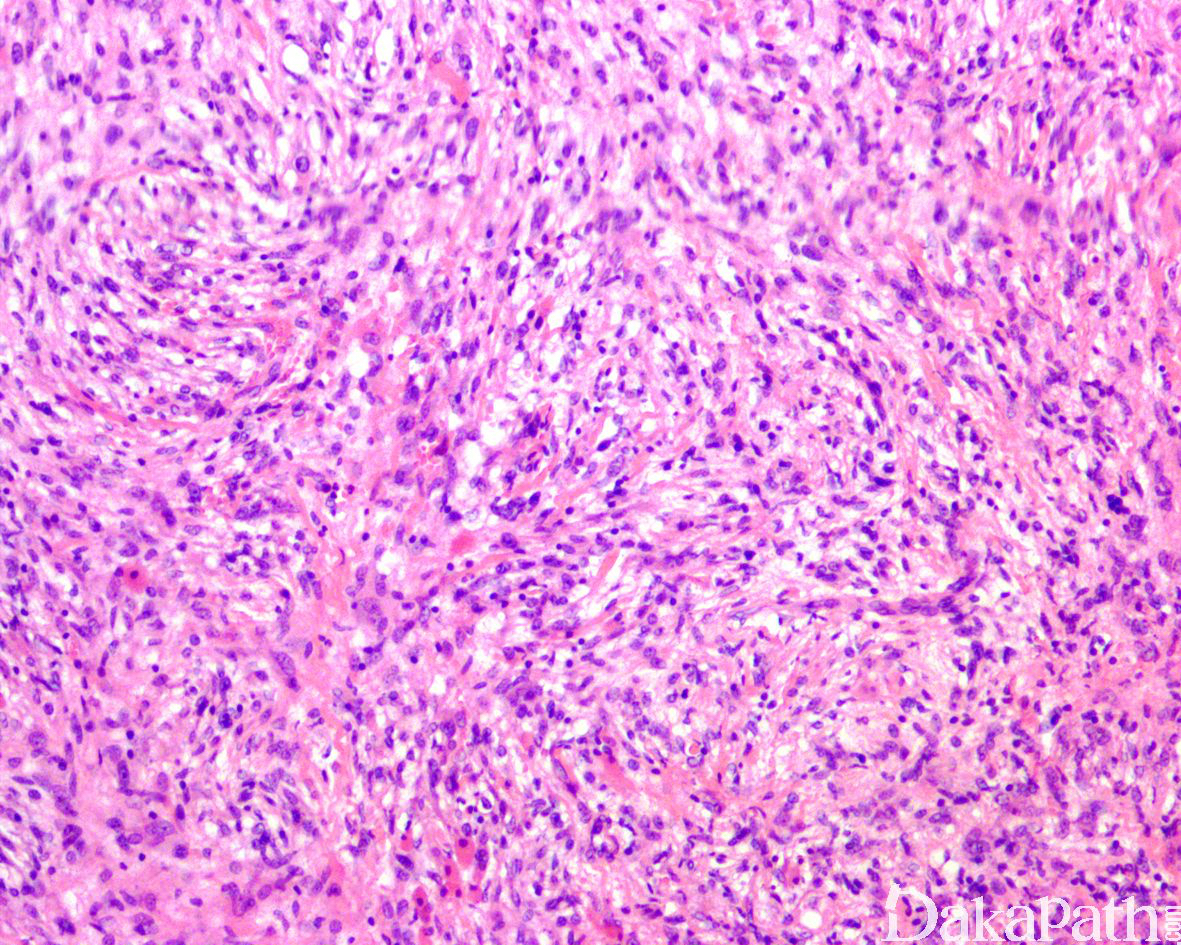

杂合性神经鞘瘤/神经束膜瘤的肿瘤细胞呈席纹状、旋涡状、层状排列,梭形瘤细胞具有少量浅嗜酸性的胞浆,细胞边界不清,核肥胖且两端变细。间质可见不同程度的纤维化和局灶的黏液变性。在神经鞘膜细胞之间为与之平行排列的呈两端细长而伸展的神经束膜细胞,在 HE 染色下观察可能并不明显,EMA、Claudin-1 免疫组化染色可清晰的显示(见后免疫组化染色)。

瘤细胞核形态温和,偶见退行性变的非典型性,罕见核分裂象,无肿瘤性坏死。